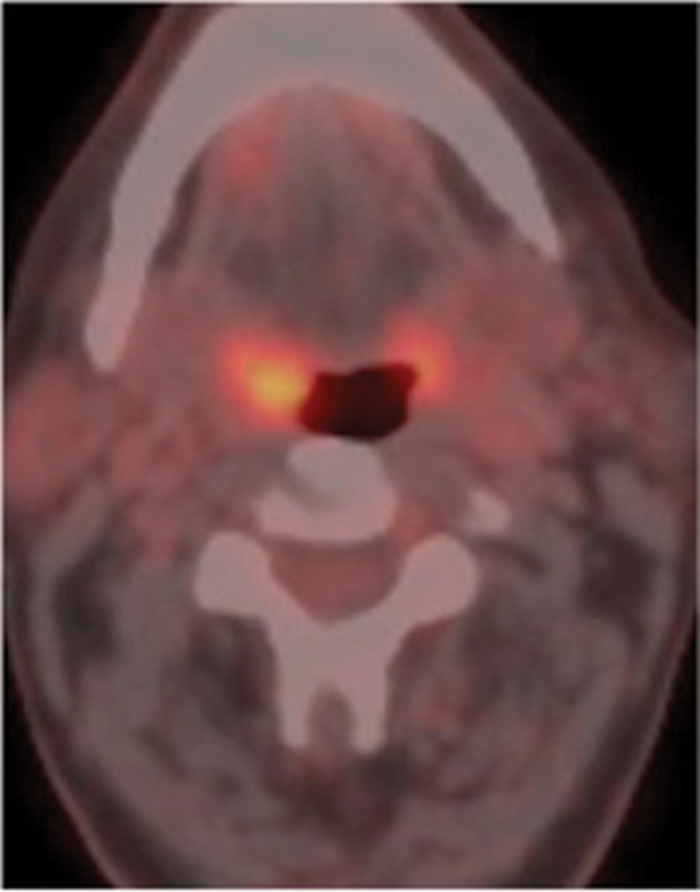

Figure 1: Patient who presented with an enlarged right level II node containing squamous cell carcinoma. No primary site was identified on usual assessment which included full clinical assessment and flexible fibre optic naso-endoscopy and head and neck MR. FDG PET-CT shows the primary site in right tonsil (arrow). Top pic = FDG, Middle pic = CT, Bottom pic =combined PET-CT.